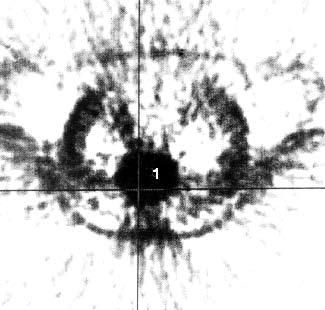

С этой целью для ПЭТ применяются радиофармацевтические препараты, меченные циклотронными радионуклидами. Возможности ПЭТ при обнаружении опухолей менее 2 см, метастазов печени, метастатических лимфатических узлов превышают таковые при КТ. Большинство исследователей применяют ПЭТ при дифференциальной диагностике злокачественных и доброкачественных образований ПЖ. В литературе имеются сведения и о возможности определения при ПЭТ степени злокачественности опухоли в зависимости от интенсивности накопления препарата. Однако для оценки резектабельности ПЭТ не может заменить КТ (рис. 103).

Кроме того, ПЭТ не позволяет поставить топический диагноз, поэтому его следует применять в сочетании с КТ. Основным недостатком исследования является необходимость использования дорогостоящей аппаратуры для производства радионуклидов, которые имеют короткий период полураспада (от нескольких минут до двух часов), что требует близкого расположения циклотрона к лаборатории (рис. 104).

Рис. 103. Компьютерная томография.

Рак тела поджелудочной железы. Видна гиподенсная опухоль тела ПЖ с неровными, бугристыми контурами 6x6 см (1)

Рис. 104. Позитронная эмиссионная томография той же больной, что и на рис. 12. В проекции выявленной на КТ опухоли отмечается очаг повышенного накопления 18Р-ФДГ диаметром 6 см с коэффициентом дифференциального накопления опухоль/нормальная ткань (КНД) 2,5–3 (1)